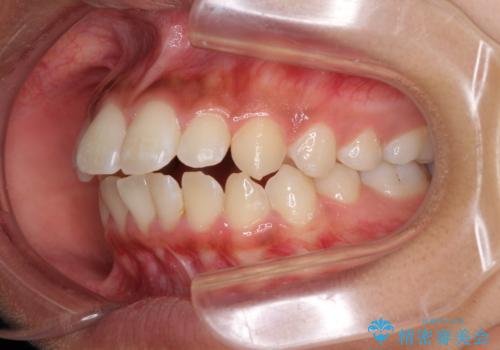

くちばしのように突出した前歯 口元を下げる抜歯矯正

- 上下の出っ歯を気にして来院された患者様です。

口元を積極的に引っ込めるために、上下左右の第一小臼歯を4本抜歯することとしました。

前歯部の突出と開咬は、舌突出癖によるものでしたので、舌のトレーニングをしっかりと行っていただき、1年半程度と短期間で治療を終えることができました。